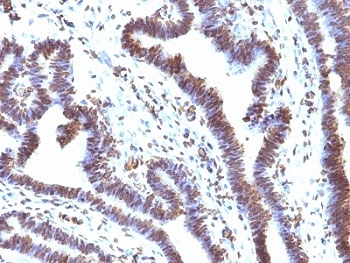

IHC: Formalin-fixed, paraffin-embedded human ovarian carcinoma stained with EMI1 antibody (clone EMI1/1176).